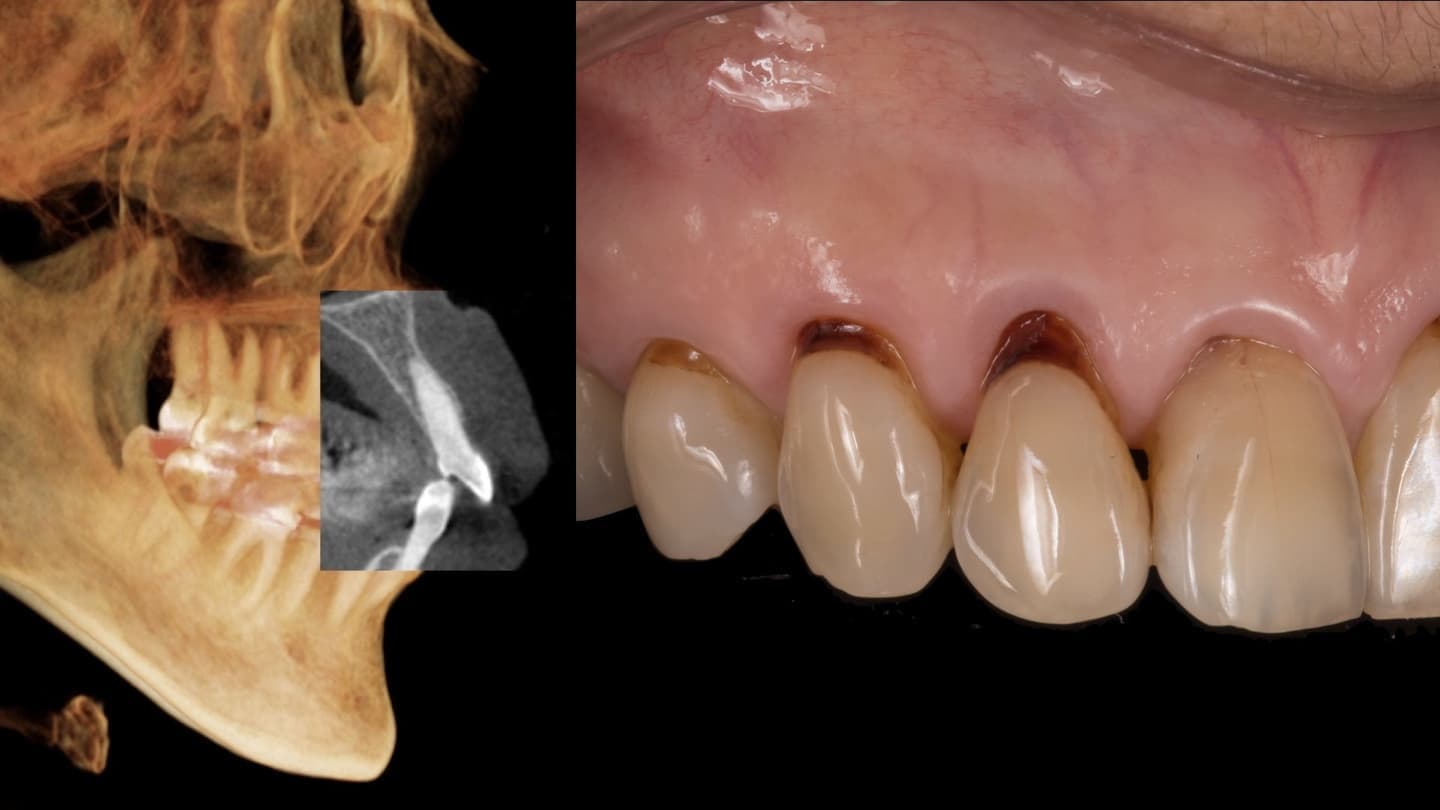

あらゆる検査からの情報を分析します

基本的な検査だけでなく、CT検査、歯周病に特異的な細菌のPCR検査、噛み合わせの検査、生活習慣の見直しなどを行います

他院では見逃してしまうケースもしっかり対応します

専門医ではないと対応できない症例もあります